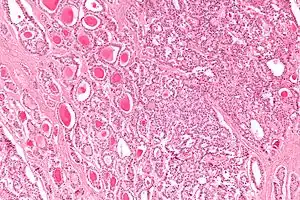

Micrograph of a strumal carcinoid. H&E stain.

The strumal carcinoid is a type of monodermal teratoma with histomorphologic features of (1) the thyroid gland and (2) a neuroendocrine tumour (carcinoid).[1][2]